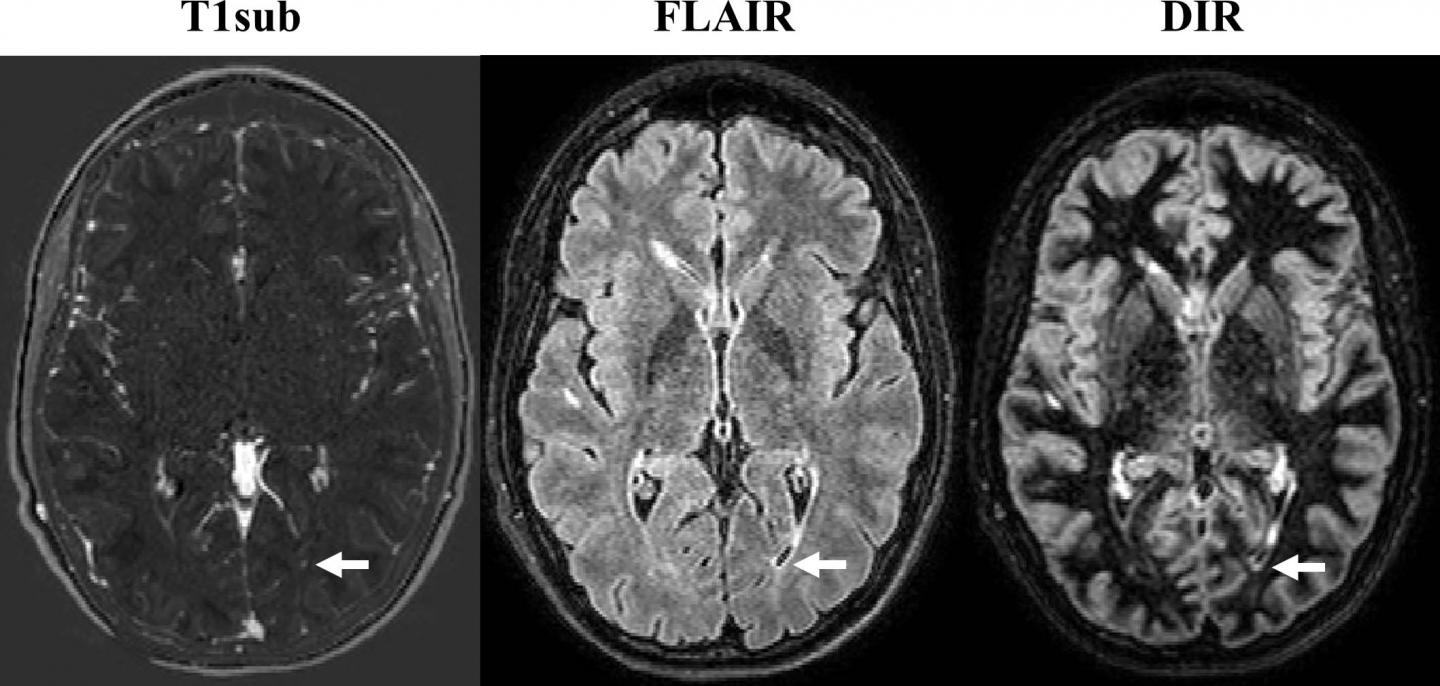

To learn more, Dr. Wiestler and colleagues used MRI to assess new or enlarged lesions in 359 patients with MS. Of 507 follow-up scans, 264 showed interval progression, defined by as at least one new or unequivocally enlarged lesion on follow-up MRI scans. There were a total of 1,992 new or enlarged lesions. With 3T MRI, the assessment of interval progression did not differ significantly between the contrast-enhanced and non-enhanced images.

"In over 500 follow-up scans, we missed only four of 1,992 new or enlarged lesions," Dr. Wiestler said. "Importantly, we did not miss disease activity in the non-enhanced scans in a single follow-up scan."

Dr. Wiestler credited an image subtraction pipeline developed and researched at his facility for the powerful sensitivity of the non-contrast MRI in detecting newly occurring lesions. The approach combines 3-D MRI and subtraction techniques, which cancel out unchanged areas in the follow-up image, substantially improving visualization of new or enlarging white matter lesions.

This combination of 3-D sequences and subtraction techniques is key to improving sensitivity for detecting newly occurred lesions, Dr. Wiestler said.